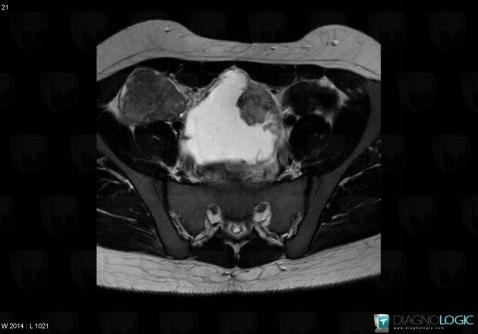

Tumeur-sac vitellin, Annexe / Ovaire - trompe, Pelvis / Périnée, IRM

Voici les informations spécifiques à l'image clé ci dessus:

- Diagnostic Tumeur du sac vitellin, Localisation(s) Annexe / Ovaire - trompe, comportant les gammes Masse annexielle solidePelvis / Périnée, comportant les gammes Masse pelvienne solide